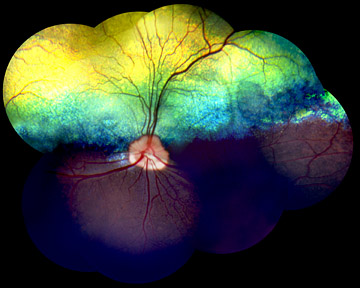

Both the canine and human inherited vision disorders involve the loss of rod cells, the photoreceptors in the eye's retina responsible for black-and-white vision and night vision, and a defect in the light-sensitive pigment in the rods, called rhodopsin. Light particles, called photons, striking rhodopsin in each of some millions of rods cause the rhodopsin protein to change shape, starting a chemical-signaling cascade that enables the brain to detect light and perceive a visual image. Then the rhodopsin molecules must regenerate to their original form in the dark. The genetic defect blamed for some forms of RP in humans and PRA in dogs produces a mutated form of rhodopsin that appears unable to regenerate properly.

"Most of us have a little trouble seeing in a darkened theater when we first come inside from the bright light," explains Gustavo D. Aguirre, the Caspary Professor of Ophthalmology in Cornell's College of Veterinary Medicine. "Then rods and the rhodopsin in our eyes begin to adapt to the dim light. But in people with this form of RP and mastiffs with PRA, the rhodopsin protein is defective and rods gradually lose the ability to recover -- first in small areas, then throughout the retina -- and they lose vision altogether. "

Gregory M. Acland, another Cornell geneticist in the vision studies, explains that in one form, human RP is an early-onset disorder with rapid loss of rods throughout the retina soon after birth, whereas in another form of RP, the loss of rods begins later in life and is more gradual. This is puzzling to researchers, but also gives them hope of finding a treatment that at least will slow the course of the disease.